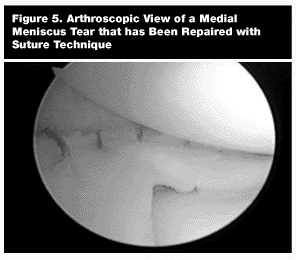

In young patients presenting after an acute injury with suspected meniscal pathology, diagnostic arthroscopy to evaluate for reparable meniscal tears is often indicated.25 (See Figure 4.) Studies have shown that loss of any portion of functional meniscus can lead to accelerated degenerative arthritis.9,25,33,34 Therefore, the meniscus should be preserved and repaired if possible.25,33 (See Figure 5.) Meniscal repairs performed in conjunction with an ACL reconstruction have much higher rates of healing.33 Not all tears are reparable and if a tear is determined to be irreparable, a partial meniscectomy should be performed attempting to preserve as much functional meniscus as possible.